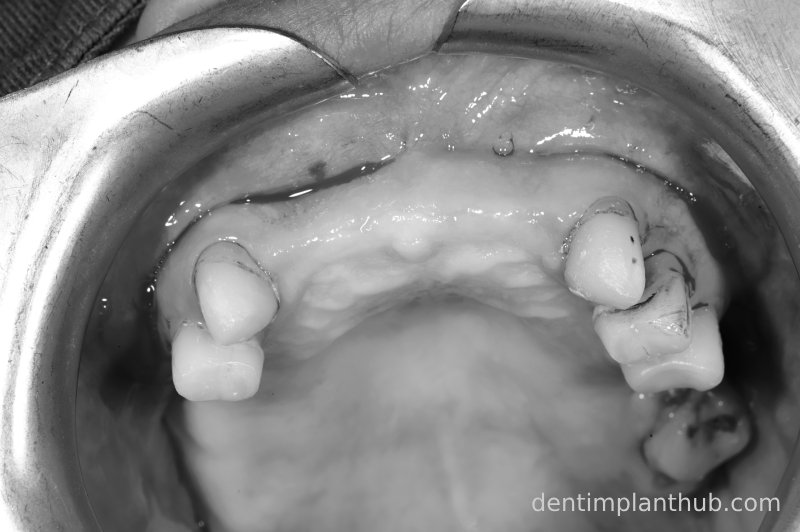

Intraoral photo before surgery on 11/10/23

Details of surgery on 11/10/23

Intraoral photograph of the upper jaw after removal of the removable denture prior to surgery on 7 June '24